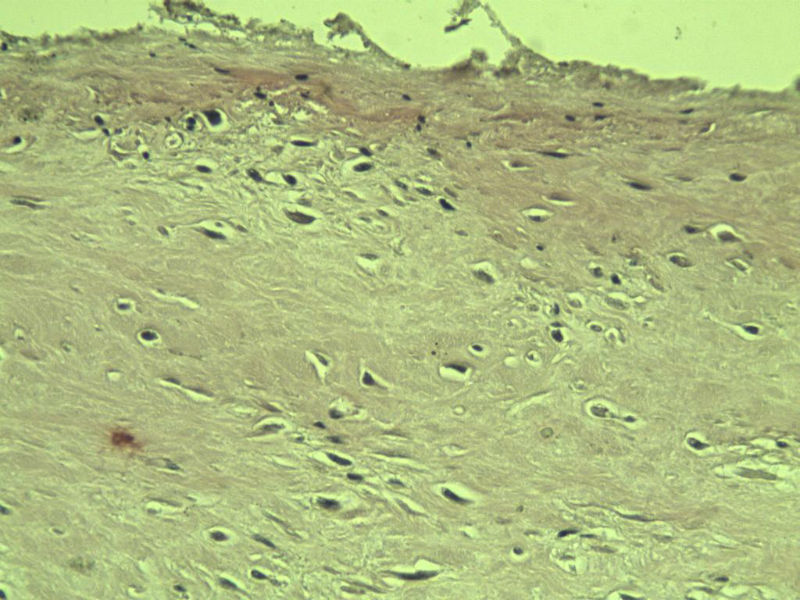

男,51岁, 4月前患者无意中发现右腘窝一包块,约核仁大小无疼痛, 4月来包块进行性生长

灰褐类圆形包块一个,直径 5 cm,切面灰白,实性,编织状。 请各位老师看看 是什么? 谢谢!